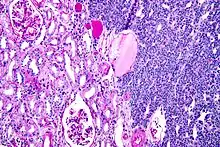

Micrograph of a metanephric adenoma with structures reminiscent of those seen in papillary renal cell carcinoma. H&E stain. | |

Metanephric adenoma (MA) is a rare, benign tumour of the kidney, that can have a microscopic appearance similar to a nephroblastoma (Wilms tumours),[1] or a papillary renal cell carcinoma.

Metanephric adenoma is diagnosed histologically. The tumours can be located at upper pole, lower pole and mid-hilar region of the kidney; they are well circumscribed but unencapsulated, tan pink, with possible cystic and hemorrhagic foci. They show a uniform architecture of closely packed acinar or tubular structures of mature and bland appearance with scanty interposed stroma.[3][4][5][6][7] Cells are small with dark staining nuclei and inconspicuous nucleoli. Blastema is absent whereas calcospherites may be present. Glomeruloid figures are a striking finding, reminiscent of early fetal metenephric tissue. The lumen of the acini may contain otherwise epithelial infoldings or fibrillary material but it is quite often empty. Mitoses are conspicuously absent.[3][4][5][6][7] In the series reported by Jones et al. tumour cells were reactive for Leu7 in 3 cases of 5, to vimentine in 4 of 6, to cytocheratin in 2 of 6, to epithelial membrane antigen in 1 of 6 cases and muscle specific antigen in 1 of 6.[5] Olgac et al. found that intense and diffuse immunoreactivity for alpha-methylacyl-CoA racemase (AMACR) is useful in differentiating renal cell carcinoma from MA but a panel including AMACR, CK7 and CD57 is better in this differential diagnosis.[8] Differential diagnosis may be quite difficult indeed as exemplified by the three malignancies initially diagnosed as MA that later metastasized, in the report by Pins et al.[9]